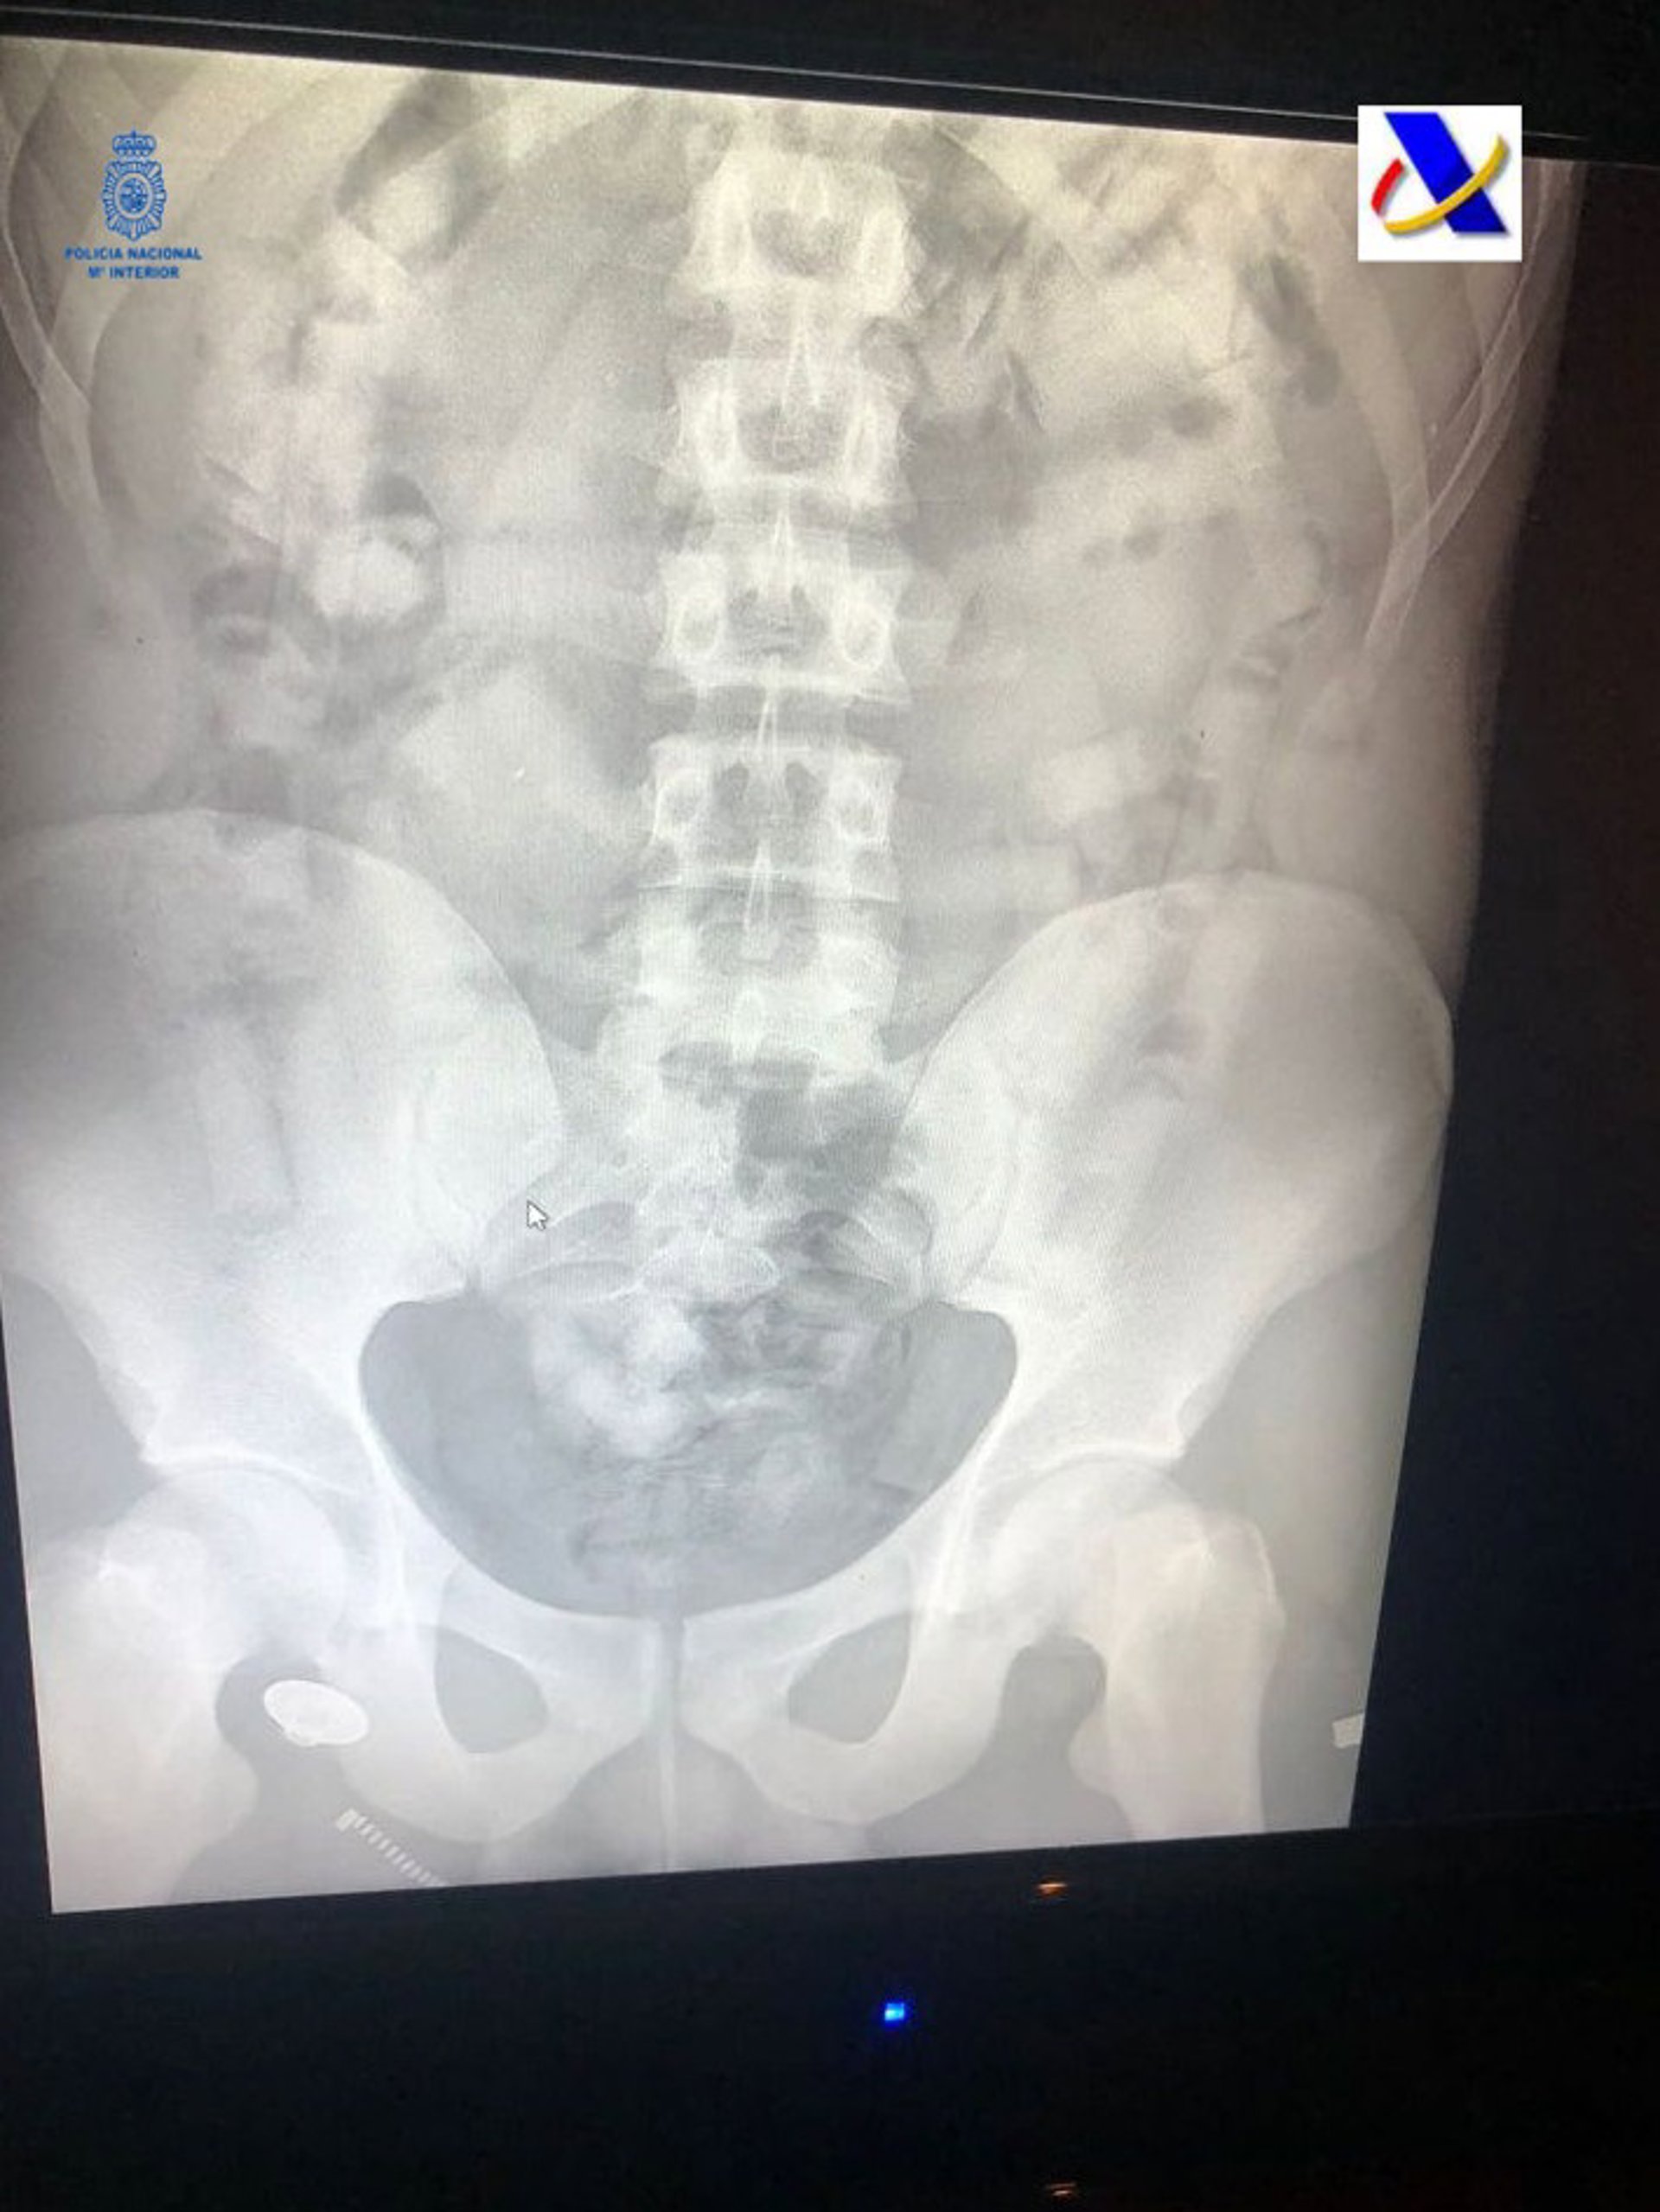

Radiografía con los cilindos de cocaína que portaba el hombre detenido en Palma.

Radiografía con los cilindos de cocaína que portaba el hombre detenido en Palma. - POLICÍA NACIONAL

Con motivo de un control en uno de los vuelos llegado de Sudamérica, fue detenido un varón del que se pudo constatar a través del sistema de rayos X que portaba droga en su cuerpo.

Una vez detenido el viajero e ingresado en el hospital fue expulsando hasta un total de 50 cilindros con cocaína, que contenían cerca de 400 gramos. Tras el incidente, el Grupo I del Grupo de Estupefacientes, se hizo cargo de las investigaciones.